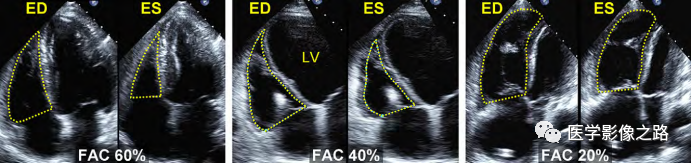

⑴面积变化率(FAC):四腔心切面,测量右室收缩期和舒张期的面积。FAC=(舒张期面积-收缩期面积)/舒张期面积。FAC>35%正常

什么叫超声容积探头医学超声影像学笔记——心脏正常的解剖和超声评价_https://www.jmylbn.com_新闻资讯_第16张